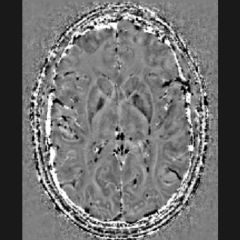

La sclérose en plaques est une maladie auto-immune liée à la présence de lésions de la substance blanche associée à une inflammation chronique induisant une démyélinisation.

Il a été montré dans les lésions actives et inflammatoires, une accumulation de fer.

Le diagnostic est basé sur l’utilisation de l’IRM pour visualiser et qualifier les lésions. Néanmoins la corrélation entre le nombre de lésions, leur types et la gravité des symptômes reste complexe à établir.

BIaaS (Brain-Iron-as-a-Service) permet de visualiser les accumulations de fer dans les lésions et de catégoriser celles-ci en termes d’activité et d’évolution. Cette solution pourrait aussi participer à la caractérisation du signe de la veine centrale (SVC).

La manifestation du fer, à travers le signe de la veine centrale et le halo paramagnétique, fait désormais partie des critères internationaux de McDonald pour diagnostiquer et suivre la SEP (version révisée en septembre 2025).